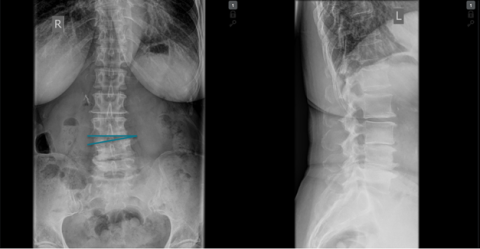

Patients who underwent microsurgical decompression using the FLA technique between 2005 and 2020 were selected to take part in the study. The coronal segmental Cobb angle (CSCA) was measured on the pre-operative, posteroanterior X-ray (Figure 2). The primary end point was the Core Outcome Measures Index (COMI) score at the two-year follow-up examination (2FU). This involved a patient questionnaire (PROM), which, alongside pain, included questions on function restrictions in day-to-life and at work, symptom-specific wellbeing and quality of life.

The final study group comprised 148 patients, whilst the control group (standard disc herniations) included 463 patients. All patients across both the study and the control group demonstrated a significant decrease in the COMI score (i.e. an improvement in their symptoms) from the pre-operative phase to the two-year check-up (p < 0.0001). Results were better (COMI score lower by 0.6 points) for patients treated at the higher lumbar vertebrae segments than those treated at the lowest level, L5/S1 (p=0.03). As well as this, in the study group, there was a statistically significant correlation between the intervertebral angle (CSCA) measured pre-operatively and the change in the COMI score two years post-operation (p < 0.001).

The association could also be found in a multiple regression analysis, which was controlled for confounding factors. An increase in the CSCA by one angular degree was linked to a 0.3 point drop in the COMI score at the 2FU (p=0.008).